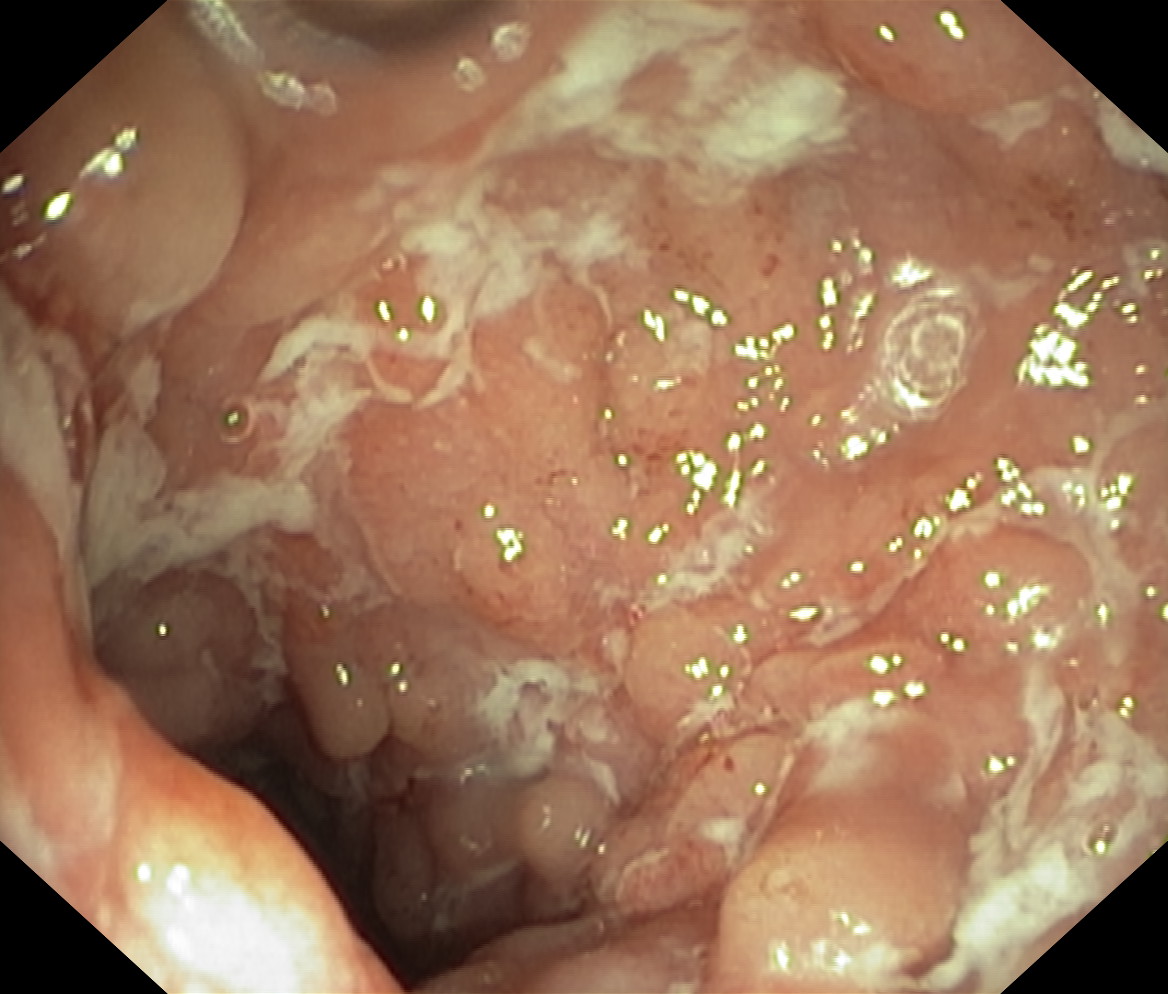

Choroba Leśniowskiego-Crohna